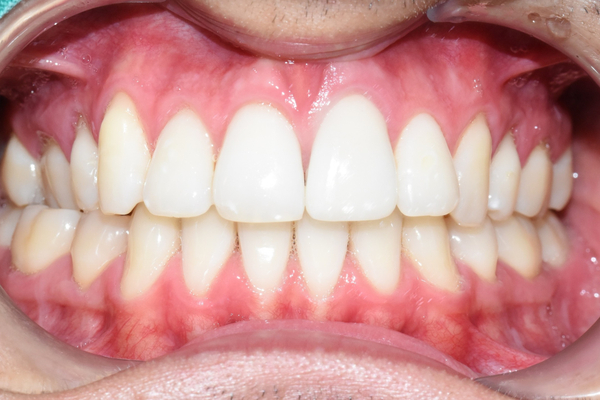

다행히 처음 끼워드린 크라운에 환자분이 색상이나 모양 매우 만족하셔서

크라운을 다시 수정보내는 일 없이 한번에 장착하였습니다.

크라운 장착 후

치료전후 사진

위 앞니 변색 치아 하나 치료 전(왼)-치료 후(오른쪽 사진)

환자분이 매우 만족하셔서 뿌듯한 케이스 였습니다.